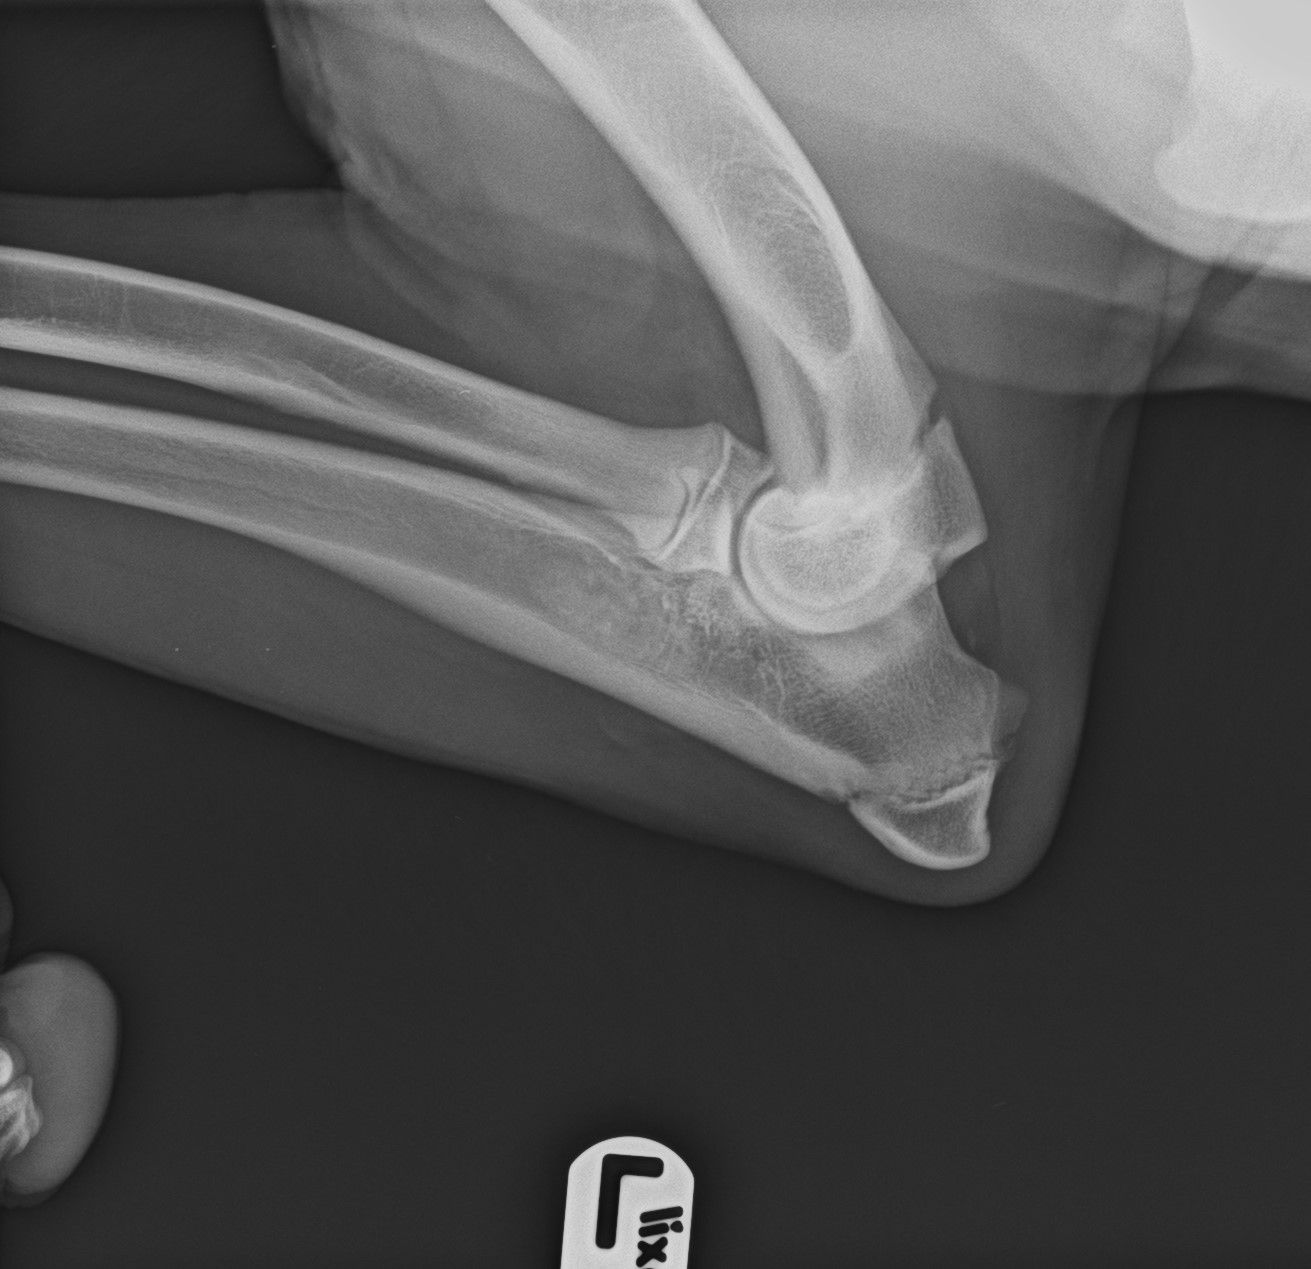

esame radiografico per displasia di anche e gomiti

DISPLASIA DELL'ANCA E GOMITO

La displasia dell'anca e del gomito sono malattie ereditarie che colpiscono i cani durante la crescita, causate da fattori genetici, ambientali, nutrizionali e traumatici, che alterano lo sviluppo articolare e portano a dolore, limitazione e artrosi.